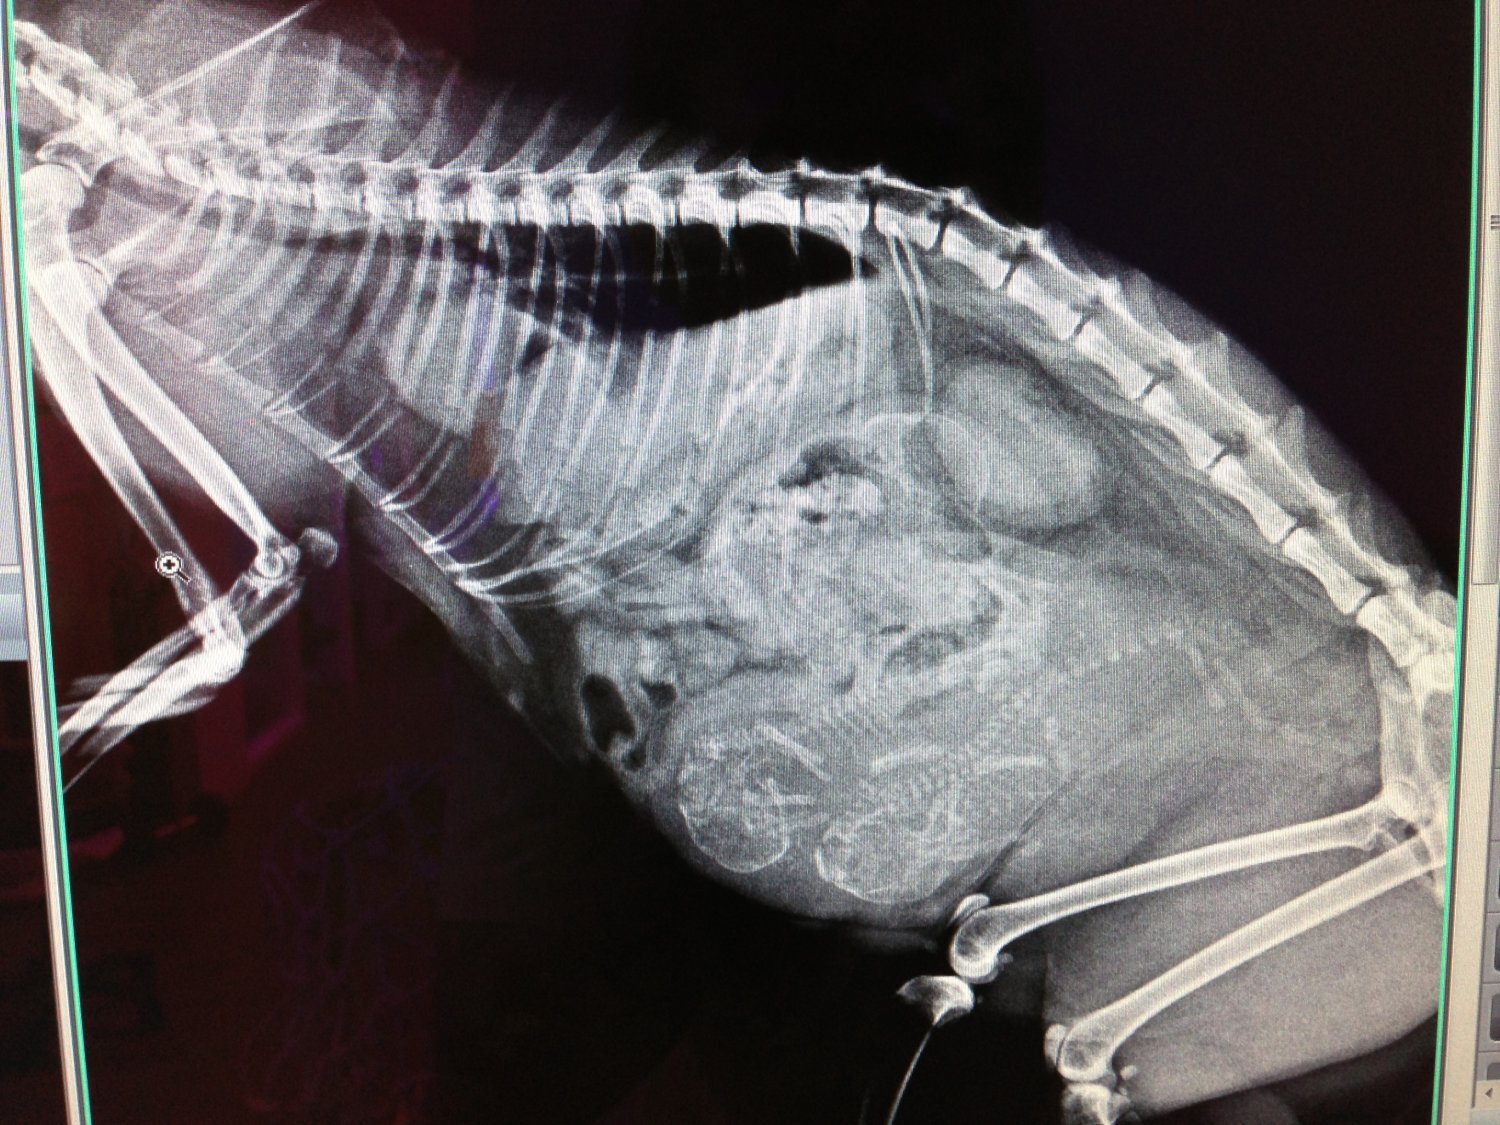

主題: 三和路難產母貓救援 申請者姓名: 臺北市支持流浪貓絕育計劃協會 花色: 申請日期: 2013-07-30 10:18:31 申請者部落格: https://www.facebook.com/SupportTNR 申請者臉書網址: 所在縣市/合作醫院: 台北市/極光動物醫院 治療費用: 39120元 需求人數: 42人 已結案 (2013-09-03 16:24:49) 報名人員: Cherry Lin x2(已付款)、Cherry Lin x2、Kim Meng(已付款)、Satine Hsu(已付款)、Elaine Yang(已付款)、Jocelyne YuYu Kao(已付款)、Li Hua(已付款)、POPO、紅色柚子(已付款)、包籠欣(已付款)、江偵安(已付款)、懂懂沒(已付款)、唐韻婷(已付款)、li(已付款)、Weiwen Tu、Weiwen Tu(已付款)、new麻(已付款)、阿短(已付款)、李璟芳(已付款)、Nico Liu(已付款)、Anq Liao(已付款)、艾維兒 x5(已付款)、Lilyanna(已付款)、gg0102(已付款)、林韋韋(已付款)、Chu(已付款)、Lydia(已付款)、Annisui Strauss(已付款)、Louise Liao(已付款)、茶茶(已付款)、Phoebe Chen(已付款)、Becca Huang(已付款)、Yegi(已付款)、Jackie Kang(已付款)、Pei-yan Wu(已付款)、Juliet(已付款)、Emily Liu(已付款)、vivian(已付款)、River Chang(已付款)、Patrick(已付款)、 候補人員: 動物病情說明: 粉絲頁面訊息通報,位在三重三和路,有隻母貓,疑似被車撞到,下體流血,

志工前去尋找,在堆滿雜物的樓梯間,發現了母貓躲藏在裡面,於是將雜物搬開

,用網子將貓網住,發現貓咪應是難產,緊急送到合作醫

院進行治療,照X光及超音波,確定是難產,肚子裡的小貓,也已都無心跳,而

且母貓還有橫隔膜疝氣(因是被車撞擊造成),也一並手術,並給予結紮,經過20天的住院治療,母

貓已完全康復,並R回原地,由原來照顧他的阿桑繼續的餵養。